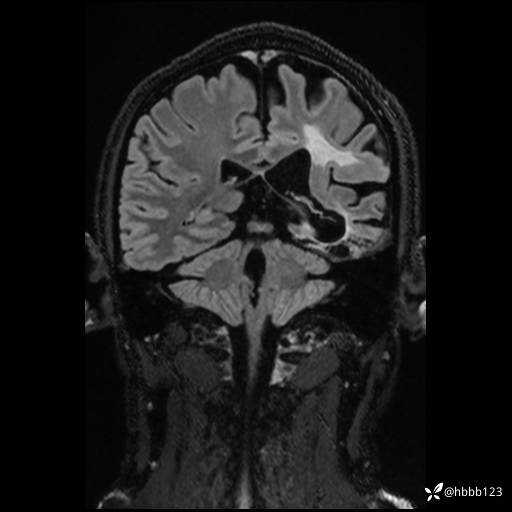

CUBE FLAIR冠状位: